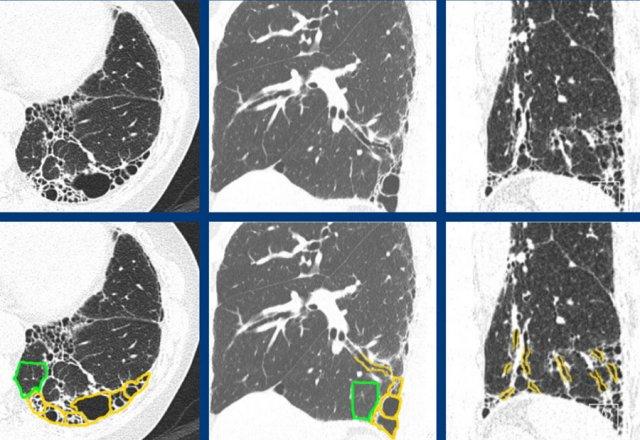

Trong A có hình ảnh tổ ong kết hợp với xơ hóa ưu thế ở nền phổi và dưới màng phổi, cho thấy hình thái UIP điển hình.

In B there is a probable UIP pattern without honeycombing.

The ongoing process of honeycombing formation. There is a spectrum ranging from normal lung tissue (A), through distortion of the secondary lobule with traction bronchiolectasis (B), to end stage cyst formation (C).

Tổ ong

là kết quả của xơ hóa tiến triển kèm theo biến dạng cấu trúc và nằm ở cuối thang điểm từ mô phổi bình thường, qua biến dạng tiểu thùy thứ cấp với giãn phế quản nhỏ do co kéo, đến hình thành nang giai đoạn cuối.